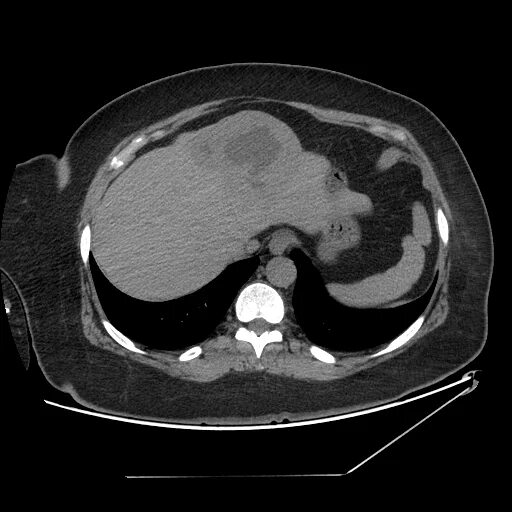

Образования печени кт